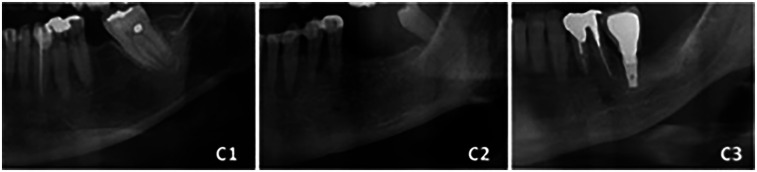

Methods: A total of 300 panoramic radiographs were analyzed. Mandibular morphometric parameters were measured, including ramus height, maximum and minimum ramus width, gonial angle, bigonial width, condylar height, coronoid height, MCW, and MCI. Statistical analysis included Spearman's correlation, multiple regression, and logistic regression to assess the relationships between mandibular morphology, cortical width, and cortical erosion with age and sex.